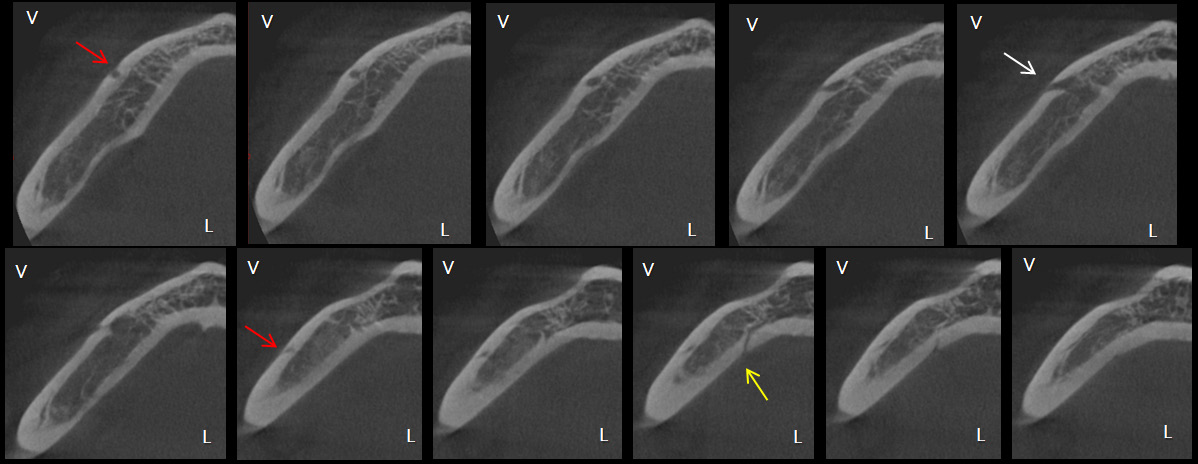

En los trabajos de Wei (16) y Krishnan (17), la variante anatómica que se observó con mayor frecuencia tanto en el lado derecho como izquierdo fue el FLL (figura 3), esto en concordancia con los resultados del presente estudio, lo que se repitió en todos los grupos etáreos. Trost (18) señaló que fueron los varones quienes presentaron mayor número de FLL en comparación a las mujeres, sin embargo, la presente investigación encontró su frecuencia en mayor porcentaje en el sexo femenino, esto podría deberse a que representaban la mayoría de la muestra. Se encontró casos con la presencia de FLL doble, no se ha hallado bibliografía que haga referencia a este tipo de variante anatómica (figura 4).

No hay mucha evidencia científica que refiera una presencia simultánea de FMA y FLL, Krishnan (17) encontró una asociación entre la presencia de ambas variantes anatómicas. En su estudio el 42,9% de los casos que presentaba FLL tenía también un FMA, este hallazgo es similar a la distribución observada en el presente trabajo (figura 6). En la muestra de este estudio se pudo encontrar combinaciones de variantes anatómicas no descritas en otras publicaciones, como la presencia de foramen doble y FLL doble en 3 casos y la relación de foramen triple y FLL encontrada en un caso (figura 7 y figura 8).